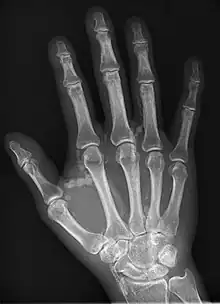

Hand radiograph showing tumoral calcinosis, PA radiograph of the right hand showing tumoral calcinosis-like metastatic calcification in a patient on dialysis. Dialysis alters calcium phosphate product (>70). Idiopathic tumoral calcinosis is autosomal dominant and is not associated with dialysis. Note the premature arterial calcification which is a clue that this is a renal patient. Vascular calcification contributes to an increase in morbidity.

Tumoral calcinosis is a rare condition in which there is calcium deposition in the soft tissue in periarticular location, around joints, outside the joint capsule.[1] They are frequently (0.5–3%) seen in patients undergoing renal dialysis. Clinically also known as hyperphosphatemic familial tumoral calcinosis (HFTC), is often caused by genetic mutations in genes that regulate phosphate physiology in the body (leading to too much phosphate (hyperphosphatemia)). Best described genes that harbour mutations in humans are FGF-23,[2] Klotho (KL),[3] or GALNT3.[4] A zebrafish animal model with reduced GALNT3 expression also showed HFTC-like phenotype,[5] indicating an evolutionary conserved mechanism that is involved in developing tumoral calcinosis.